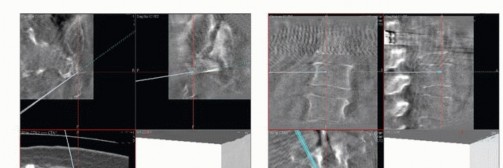

قطع العظم العجزي

يتم تحديد مستوى قطع العظم العجزي بدقة باستخدام الكي الكهربائي، بقياس المسافة بين العصعص والمستوى المخطط له قبل الجراحة. تُقطع عضلات الألوية الكبرى على بعد 1 سم من نقطة ارتباطها بالعجز. تُربط الأوعية الدموية في عضلات الألوية بعناية. تُفصل عضلات الظهر المنتصبة إذا لم تكن متورطة.

بعد قطع الأربطة من الجوانب الأمامية والجانبية للعصعص، يتم دفع الأنسجة الدهنية الصفراء الموجودة أمام العجز أماميًا لخلق مساحة لقطع ارتباطات عضلات قاع الحوض في العجز. ثم يتم قطع الرباط العجزي الحدبي والرباط العجزي الشوكي.

يتم بعد ذلك كشف العضلة الكمثرية. تُطبق شاشات مبللة في الفضاء أمام العجز لتشريح كبسولة الورم الكاذبة من المستقيم. بعد تقسيم الرفاء العصعصي الشرجي، يتم إجراء تشريح لطيف بالأصابع لمسافة قصيرة على السطح الأمامي للأمعاء حتى يتم الوصول إلى مستوى التش